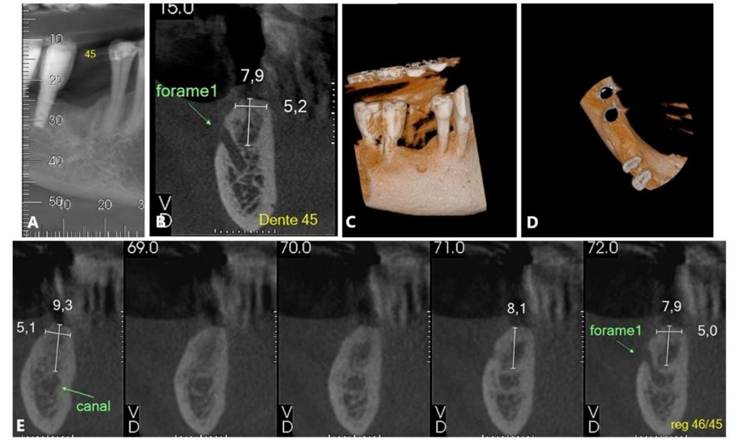

Foram solicitados exames complementares, incluindo radiografia panorâmica e tomografia computadorizada, para avaliação precisa da região anatômica, permitindo a quantificação da espessura e altura óssea (Figura 01. A-D). O plano de tratamento consistiu pela instalação de implantes ultrashort ARCSYS (FGM, Joinvile – SC, Brasil) 4,3 mm x 5,0 mm.

Figura 01. A – D) Exames de imagem complementares evidenciado aspecto inicial da região atrófica na maxila superior direita (área do elemento dental 16).